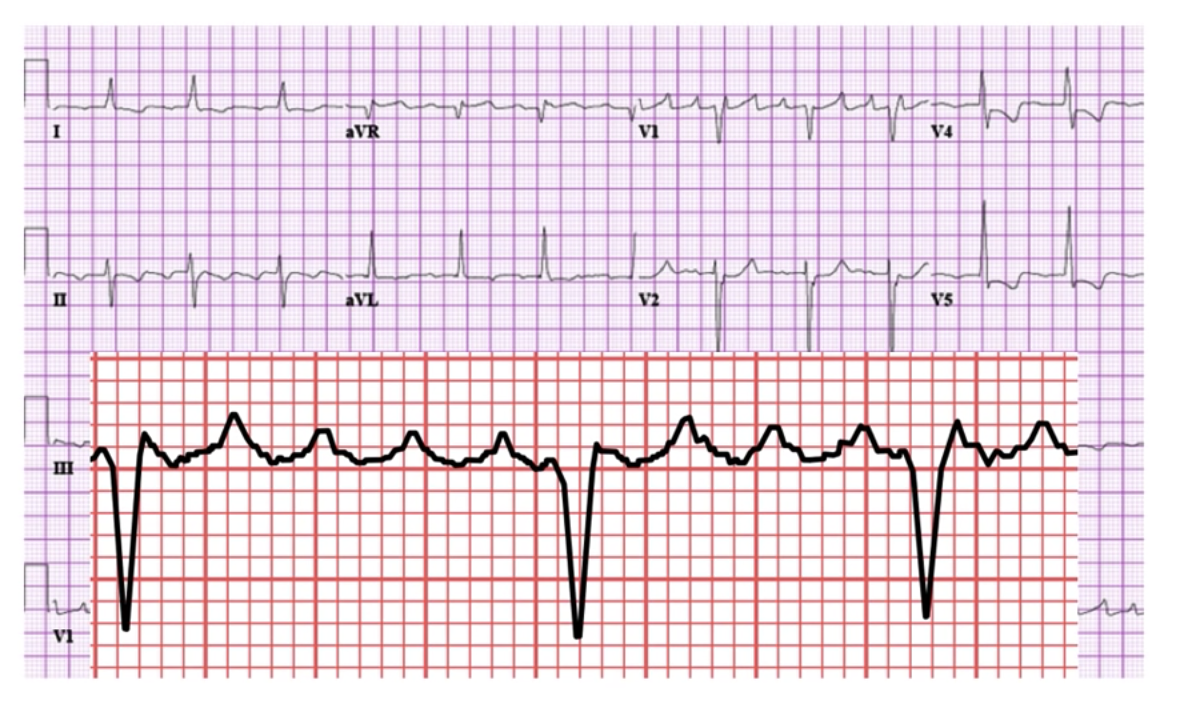

Pericarditis:

Diffuse ST-elevation in ALL leads (red)

Diffuse PR- depression (blue)